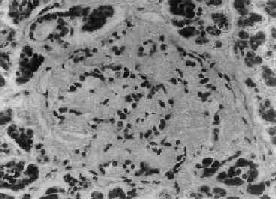

1.胰岛的病变不同类型的糖尿病及其不同时期,病变差异甚大。Ⅰ型糖尿病早期可见胰岛炎,胰岛内及其周围有大量淋巴细胞浸润,偶见嗜酸性粒细胞。胰岛细胞进行性破坏、消失,胰岛内A细胞相对增多,进而胰岛变小,数目也减少,有的胰岛纤维化;Ⅱ型糖尿病用常规方法检查时,早期几无变化,以后可见胰岛B细胞有所减少。常见变化为胰岛淀粉样变,在B细胞周围及毛细血管间有淀粉样物质沉着(图15-18),该物质可能是胰岛素B链的分解产物。

图15-18 糖尿病之胰岛

图示胰岛淀粉样变